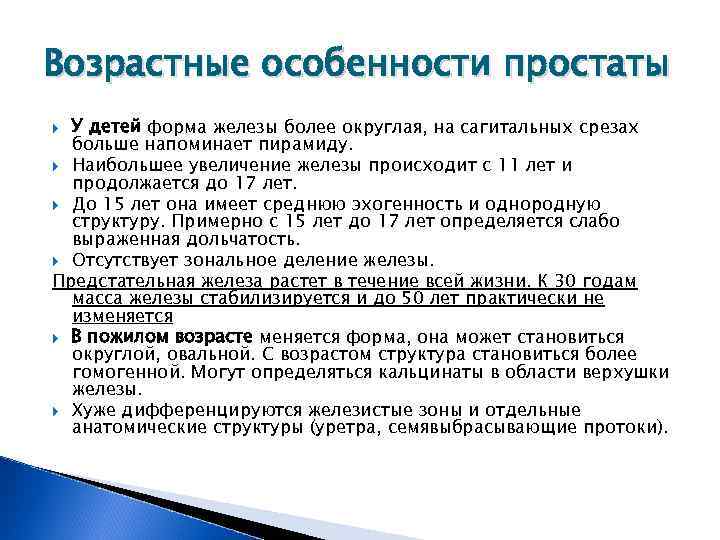

Простата детей